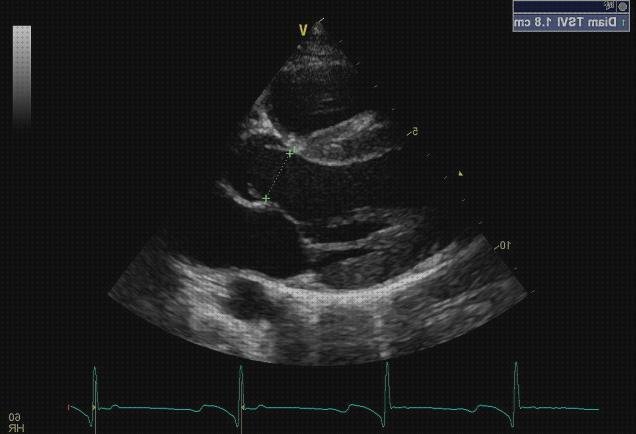

Generalmente se hace sobre la piel, colocando un gel acuoso que sirve de tocamiento con el transductor que maneja el médico, el que visualiza las imágenes en una monitora. Para ciertas órganos resulta necesario ingresar transductores particulares en el recto o la vagina, así está ocurriendo en los estudios de próstata o ginecológicos.

El médico puede observar los órganos y sus lesiones y solidificar la imagen en la región que desea analizar, medir cuantificando cambios y también expresar. Su propia app más popular es en el campo del obstetricia para el diagnóstico y acoso del estorbo. Pero casi todos las regiones del cuerpo excepto excepciones pueden llegar a ser evaluadas por ecografía.

¿para qué exactamente sirve?

Una ecografía doppler se emplea para identificar el flujo sanguíneo que a su vez puede contribuir a establecer una multitud de molestias incluyendo coágulos sanguíneos, arterias bloqueadas o angostas y aneurismas (arterias protuberantes) entre otras. También puedes usar para supervisar el flujo sanguíneo después de una cirugía e incluso para controlar la salud de un bebé antes de empezar. ¿cómo comenzar para esto? El sistema es no invasiva y se preciso muy poca preparación. Se recomienda ropa suelta y posiblemente sea obligatorio tomar los objetos tales como corbatas o intermedios, ya que hay que llevar un dispositivo sobre el cutis. También puede llegar a ser obligatorio dejar de aspirar, ya que la nicotina puede reducir los vasos sanguíneos.